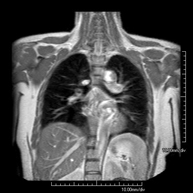

- RM Mediastino

Prueba diagnóstica no invasiva que consiste en la obtención de imágenes de alta definición anatómica del mediastino mediante el empleo de un campo electromagnético y ondas de radio (con un emisor y un receptor). No utiliza radiación ionizante. El mediastino es la parte central de la caja torácica que incluye el timo, los grandes vasos (aorta torácica, vena cava inferior y superior, etc.), el corazón, la tráquea y los bronquios principales, ganglios linfáticos mediastínicos e hiliares, el esófago, etc. Está especialmente indicada en lesiones mediastínicas para diferenciar si son quísticas o sólidas, en el diagnóstico diferencial de las lesiones del mediastino anterior, etc. En ocasiones se deberá emplear contraste paramagnético (Gadolinio) para completar el estudio. - RM Tórax

Prueba diagnóstica no invasiva que consiste en la obtención de imágenes de alta definición anatómica del tórax mediante el empleo de un campo electromagnético y ondas de radio (con un emisor y un receptor). No utiliza radiación ionizante. Está indicada en aquellas lesiones pulmonares en las que debe descartarse si existe infiltración del mediastino o de la pared torácica, para diferenciar si una lesión torácica es sólida o quística, etc. En ocasiones se deberá emplear contraste paramagnético (Gadolinio) para completar el estudio. - RM Pared Torácica

- RM Tórax

Prueba diagnóstica no invasiva que consiste en la obtención de imágenes de alta definición anatómica del tórax mediante el empleo de un campo electromagnético y ondas de radio (con un emisor y un receptor). No utiliza radiación ionizante. Está indicada en aquellas lesiones pulmonares en las que debe descartarse si existe infiltración del mediastino o de la pared torácica, para diferenciar si una lesión torácica es sólida o quística, etc. En ocasiones se deberá emplear contraste paramagnético (Gadolinio) para completar el estudio. - RM Abdomen